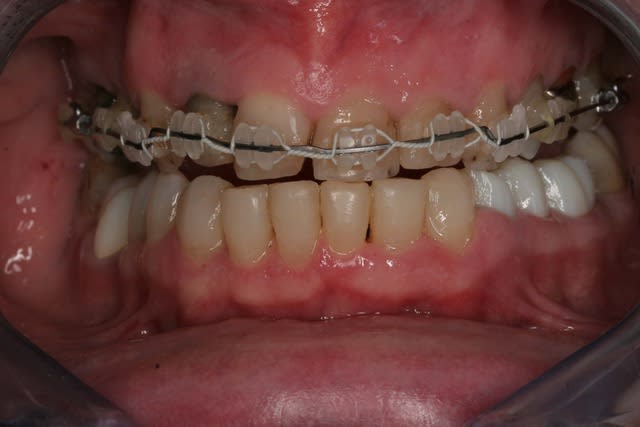

Donc la suite, évidement ortho: ingression du bloc incisivo canin sup avec ré alignement des arcades, extraction de la 14 nécessaire et ré alignement des milieux interincisif.

Pendant la finalisation du haut (axe mésio-disto incisif, à corriger à la fin pour faciliter gingivoplastie incisif sup). Il y a eu composite vestibulaire pelliculaire sous digue de 33 à 43, reprise soins et ancrage + provisoires 34,35, 36, 46; et composite sous digue 37 et 47.

Si bien sûr, sur les photos le bas venait juste d'être déposé, pour le montage composite, la patiente retournait le lendemain chez l'ortho pour placer une contention (celles que je fais avec l'Everstik me semble moins costaud que les siennes avec un fil titane), on devine un peu les faces vestibulaires des inf sur les photos pstés précédement, elles ont un sorte de crevace les striant de mesial à distal à mi hauteur, avec des petits trous colorés brun , mais pas de lésion carieuse ni de restauration ancienne. Le haut devait être déposé dans la foulé mais l'axe mésio-distal des 11 et 21 était trop couché et c'est moche (effet d'essuie glace) donc le multibague haut est resté quelques semaines de plus, d'où les photos mixte soins bas ortho haut.